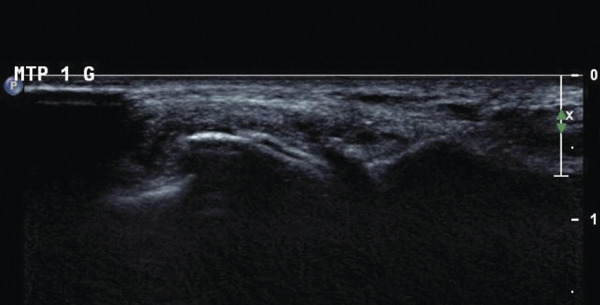

L’échographie peut montrer un aspect dit en « double contour » (fig. 5), correspondant à des dépôts uratiques à la surface des cartilages hyalins et un aspect de synovite en « tempête de neige » chargée en cristaux d’urate.

Il s'agit d'un examen très performant, et plus sensible pour détecter des dépôts que la radiographie qui ne montre que des signes indirects à un stade évolué. De plus l'échographie semble être un outil de choix pour monitorer la dissolution des cristaux sous traitement hypouricémiant (disparition des doubles contours, réduction puis disparition des tophus). Enfin le le scanner double énergie, disponible dans certains centres, permet parfois de mettre en évidence avec une très bonne spécificité, des dépôts d'urate de sodium dans des localisations plus difficiles à explorer en échographie comme le rachis. Il s'agit d'un outil permettant aussi de quantifier le volume des dépôts.